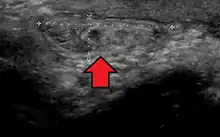

In the diagnosis of abdominal hernias, imaging is the principal means of detecting internal diaphragmatic and other nonpalpable or unsuspected hernias. Multidetector CT (MDCT) can show with precision the anatomic site of the hernia sac, the contents of the sac, and any complications. MDCT also offers clear detail of the abdominal wall allowing wall hernias to be identified accurately.[17]